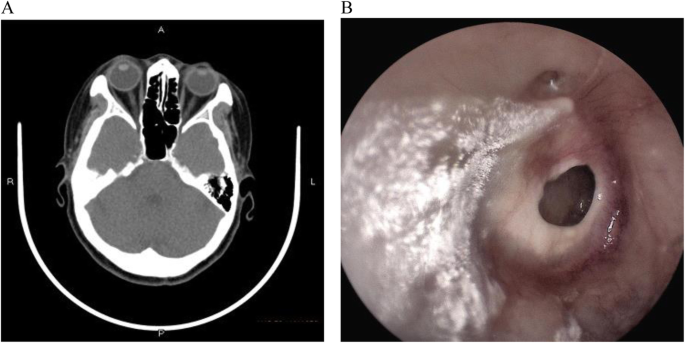

2.3 Viêm tai giữa mạn tính (giai đoạn nặng, có nguy cơ biến chứng)

Khi bệnh kéo dài mà không được điều trị đúng cách, hình ảnh viêm tai giữa ở người lớn trong giai đoạn này cho thấy tổn thương nghiêm trọng tại màng nhĩ và các cấu trúc tai giữa. Vi khuẩn có thể lan rộng, gây ra nhiều biến chứng nguy hiểm.

Dấu hiệu nhận biết qua hình ảnh

• Xuất hiện lỗ thủng trên màng nhĩ, có thể thấy dịch mủ chảy ra ngoài.

• Dịch mủ có màu vàng đậm hoặc xanh, đôi khi có mùi hôi do nhiễm khuẩn.

• Tổ chức xơ sẹo hoặc tổn thương tại khoang tai giữa, dấu hiệu của tình trạng viêm nhiễm kéo dài.

Hình ảnh viêm tai giữa ở người lớn giai đoạn mạn tính (Ảnh: Researchgate)

(*) Ghi chú:

(A) Viêm tai giữa mạn tính không hoạt động bên trái.

(B) Viêm tai giữa mạn tính hoạt động bên phải, với màng nhĩ bị viêm và niêm mạc tai giữa ẩm ướt. Hình ảnh nội soi tai sau phẫu thuật vá màng nhĩ (tympanoplasty) sau 3 tháng theo dõi

(C) Viêm tai giữa mạn tính không hoạt động dạng niêm mạc

(D) viêm tai giữa mạn tính hoạt động dạng niêm mạc